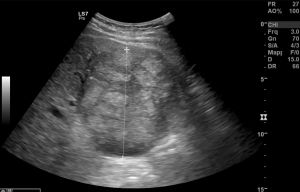

Ad oggi sono state identificate con l’ecografia addominale prevista dal protocollo, 9 neoplasie del parenchima epatico: 5 angiosarcomi (Fig. 1-4) (di cui 2 viventi) e 4 epatocarcinomi (Fig. 5-7) (di cui 1 vivente), successivamente sottoposte a studio TC e tutte confermate dalla diagnosi istologica.

Fig.3. Caso 2 di angiosarcoma epatico

Fig.4. Caso 2 di angiosarcoma epatico